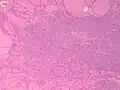

Fine-needle aspiration for cytology is generally not indicated in an autonomously functioning thyroid nodule, as the risk of malignancy is low, and it is generally difficult to distinguishing between a benign lesion and a malignant lesion in such specimens.[8] If thyroidectomy is performed, histopathology can corroborate the diagnosis. Toxic multinodular goiter more or less corresponds to diffuse or multinodular hyperplasia of the thyroid (Grave's disease also shows hyperplasia, but typically more prominent thickening of follicular linings):